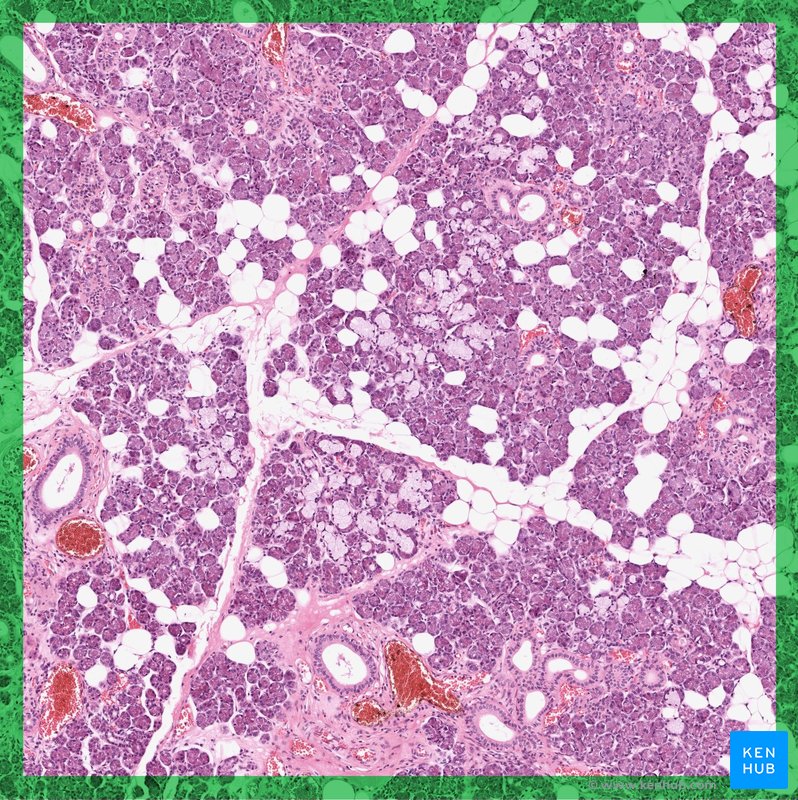

Pancreas

The pancreas is an organ comprised of both exocrine and endocrine glands. The majority of the pancreas has an exocrine function and secretes an enzyme-rich alkaline fluid into the pancreatic duct, which joins the common bile duct before emptying into the duodenum. The exocrine glands secrete the proteolytic enzymes trypsinogen and chymotrypsinogen, which are activated to trypsin and chymotrypsin in the duodenum and aid in digestion.

The exocrine pancreas also secretes bicarbonate ions, which neutralise the acidic chyme as it reaches the duodenum. There are also clusters of endocrine glands located within the exocrine tissue and these are referred to as islets of Langerhans. The two main hormones released from the endocrine glands of the pancreas are insulin and glucagon. The pancreas also secretes: